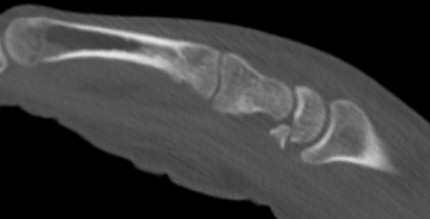

Fraktur i volara polen efter högenergitrauma

Skada: Fraktur lunatum

- Dorsala polen

- Korpus

- Volara polen